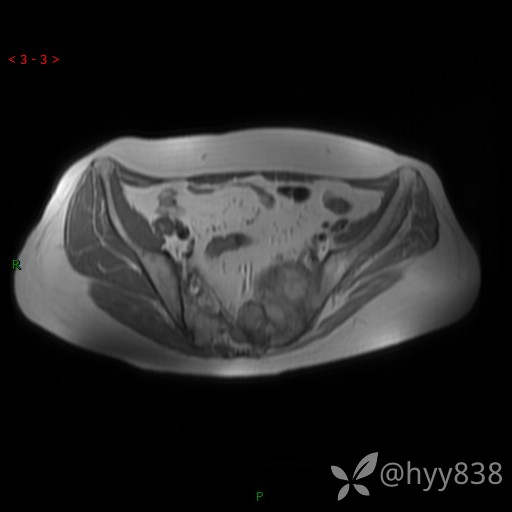

骨盆MRI平扫(T1WI+T2WI+DWI)(外院CT,不能上传)